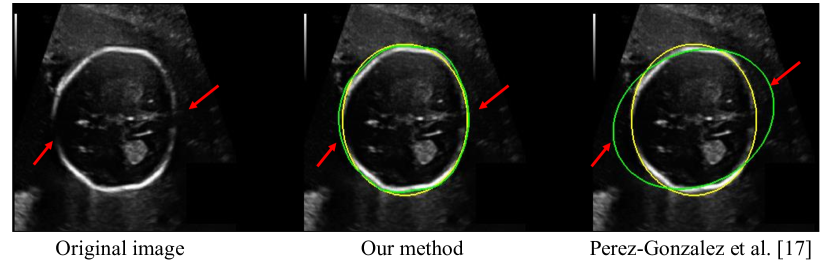

In the iterative training process, we also replaced our pseudo labels obtained by with those obtained by existing unsupervised methods, i.e., [56] for optic disc and [17] for fetal head, which is denoted as [56] + IT + wDice and [17] + IT + wDice, respectively. Table 4 demonstrates that when pseudo labels obtained by [17] or [56] are used, our iterative training still leads to a large performance improvement. However, the performance is worse than using pseudo labels obtained by our for the iterative training process. Table 4 also shows that the result of our method has no significant difference from that of learning from human annotations for optic disc segmentation, and the performance gap is also subtle for fetal head segmentation. Visual comparison in Fig. 10 shows that the result of our method is comparable to that of learning from human annotations and Fig. 11 shows that our method performs well when dealing with images with weak boundary information like fetal head segmentation.